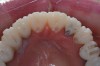

Figure 4  Interocclusal registration made at the approximate OVD for rehabilitation.

Figure 4

Figure 5  Accurate casts mounted at arbitrary OVD.

Figure 5